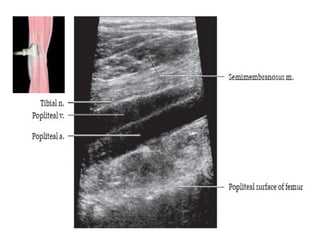

Tibial Nerve

• Largest division of sciatic nerve.

• Arises from ventral surface of sacral plexus(L4-S3) and runs

medially.

• Courses through the popliteal fossa passing deep to

gastrocnemius muscle.

04/29/2025 22

• It passes inferiorly between the heads of gastrocnemius and

deep to soleus muscle.

• Continues inferiorly in the midline deep to soleus and

superficial to the tibialis posterior muscle.

• At the ankle passes under flexor retinaculum in the tarsal

tunnel.